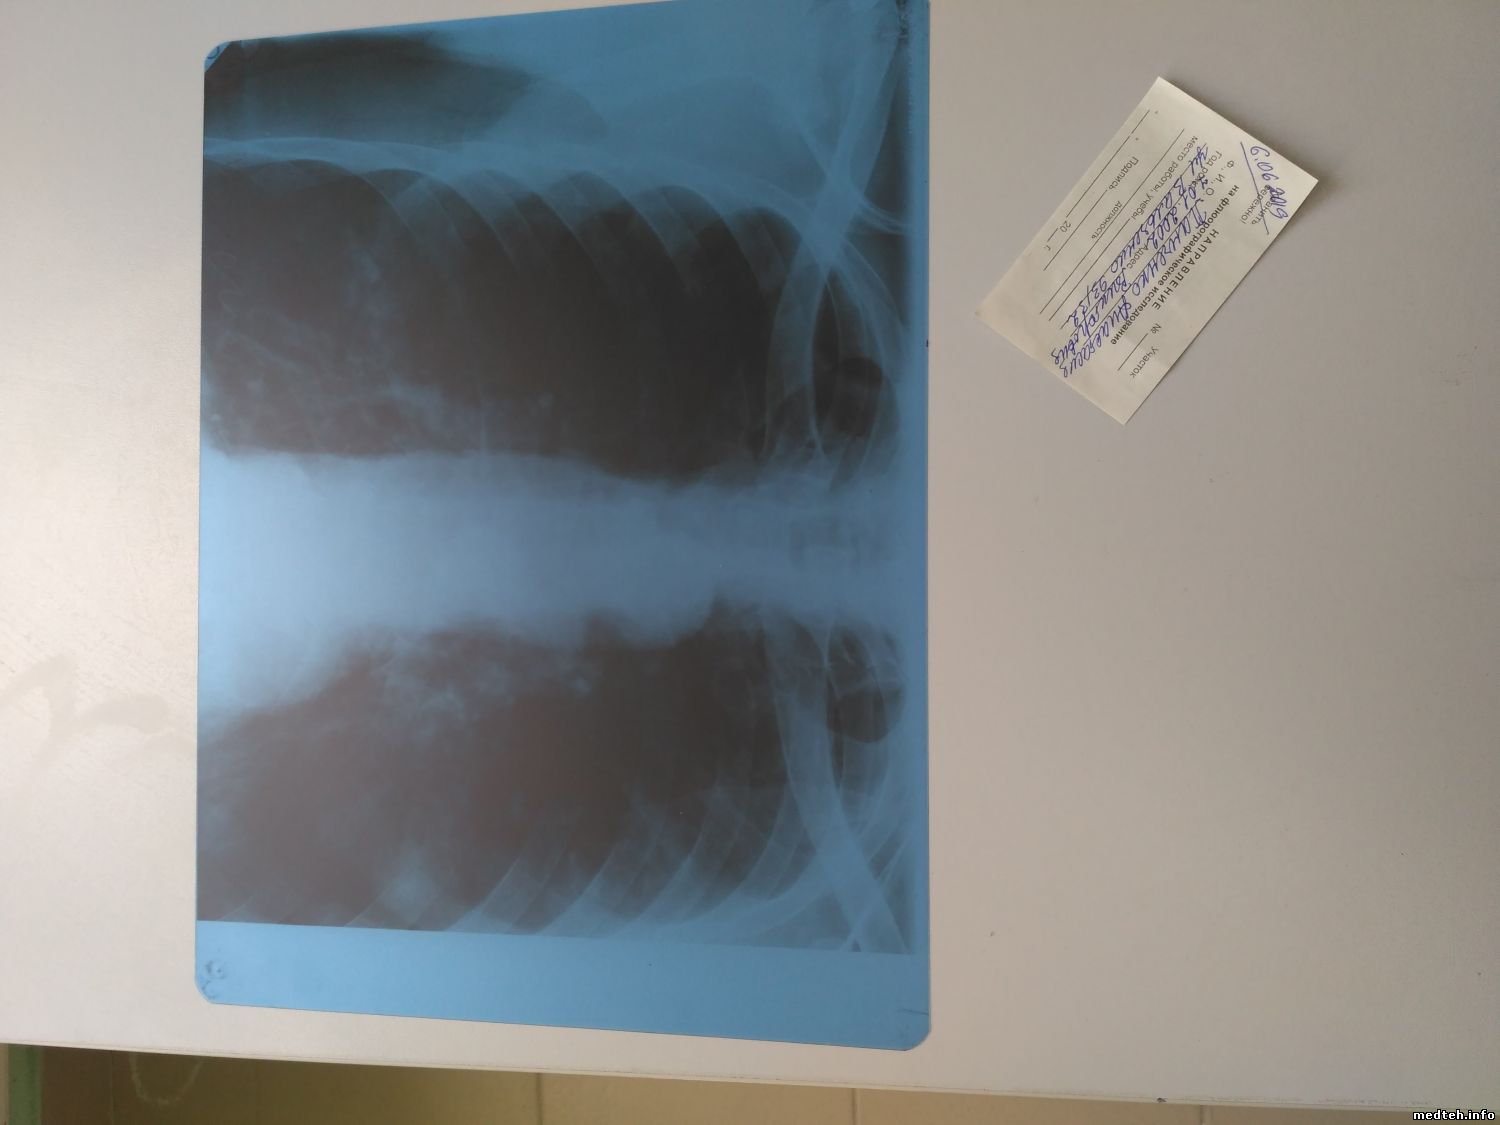

обрезка выглядит так:

9825084.jpg (85.0 Kb)